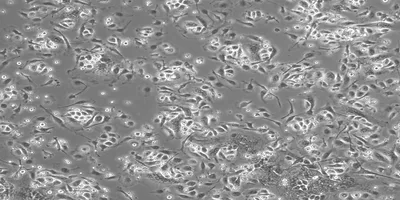

University of Edinburgh’s hepatologist and liver disease researcher, Stuart Forbes and his colleagues are exploring the regenerative properties of macrophages to treat severe liver disease.

Forbes lab group